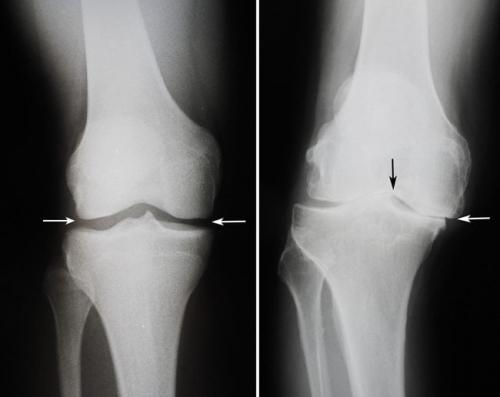

- дегенеративно-дистрофические. Чаще встречаются у пожилых людей и лиц, которые постоянно выполняют тяжелую физическую работу. Дегенеративные процессыэто следствие старения организма, которое сопровождается замедлением метаболизма и кровообращения в суставах. Под действием провоцирующих факторов (физические нагрузки, нехватка кальция, обменные нарушения) суставные хрящи начинают разрушаться, что приводит к развитию патологии. Дегенеративно-дистрофические заболевания имеют хроническое, медленно прогрессирующее течение;